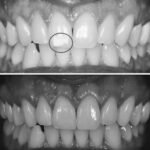

במרפאת שיניים ד"ר ממלידר בהוד השרון מתמחים בעזרה ראשונה חירום ושירותי שיקום הפה. הצוות המקצועי מציע טיפולים מתקדמים כמו הלבנת שיניים בלייזר, שמשדרגת את החיוך שלכם בשיטות מת modernas ויעילות. תחום ההתמקצעות של המרפאה והמחויבות לאיכות הטיפול מקנים למטופלים חוויה נינוחה ובטוחה.

מרפאת שיניים ד"ר ממלידר מציעה שירותים רפואיים מקצועיים בתחום הדנטלי. עם מיקום נוח בכתובת ישורון 45 א, הוד השרון, מרפאה זו מתמחה במגוון רחב של טיפולים, כולל שיקום הפה, הלבנת שיניים בלייזר, ושירותי עזרה ראשונה חירום.

המרפאה מתהדרת בציוד חדיש ובטכנולוגיות מתקדמות, אשר מאפשרות לה להעניק טיפולים איכותיים ומתקדמים. צוות המרפאה מורכב ממומחים בתחום הדנטלי, שמספקים תשומת לב אישית לכל מטופל, עם יחס חם ומקצועי. מפורסמת בשירותיה המצוינים, המרפאה זכתה לציון גבוה של 5.0 מתוך 5 על ידי שני לקוחות מרוצים.

ד"ר ממלידר ושאר הצוות פועלים להעניק פתרונות מותאמים אישית, עם דגש על נוחות וביטחון המטופלים. בקליניקה ישנו דגש על שיטות טיפול חדשניות, שמטרתן להקל על חווית המטופל ולצמצם ככל האפשר את הכאב והדאגה הנלווים לטיפולים דנטליים.